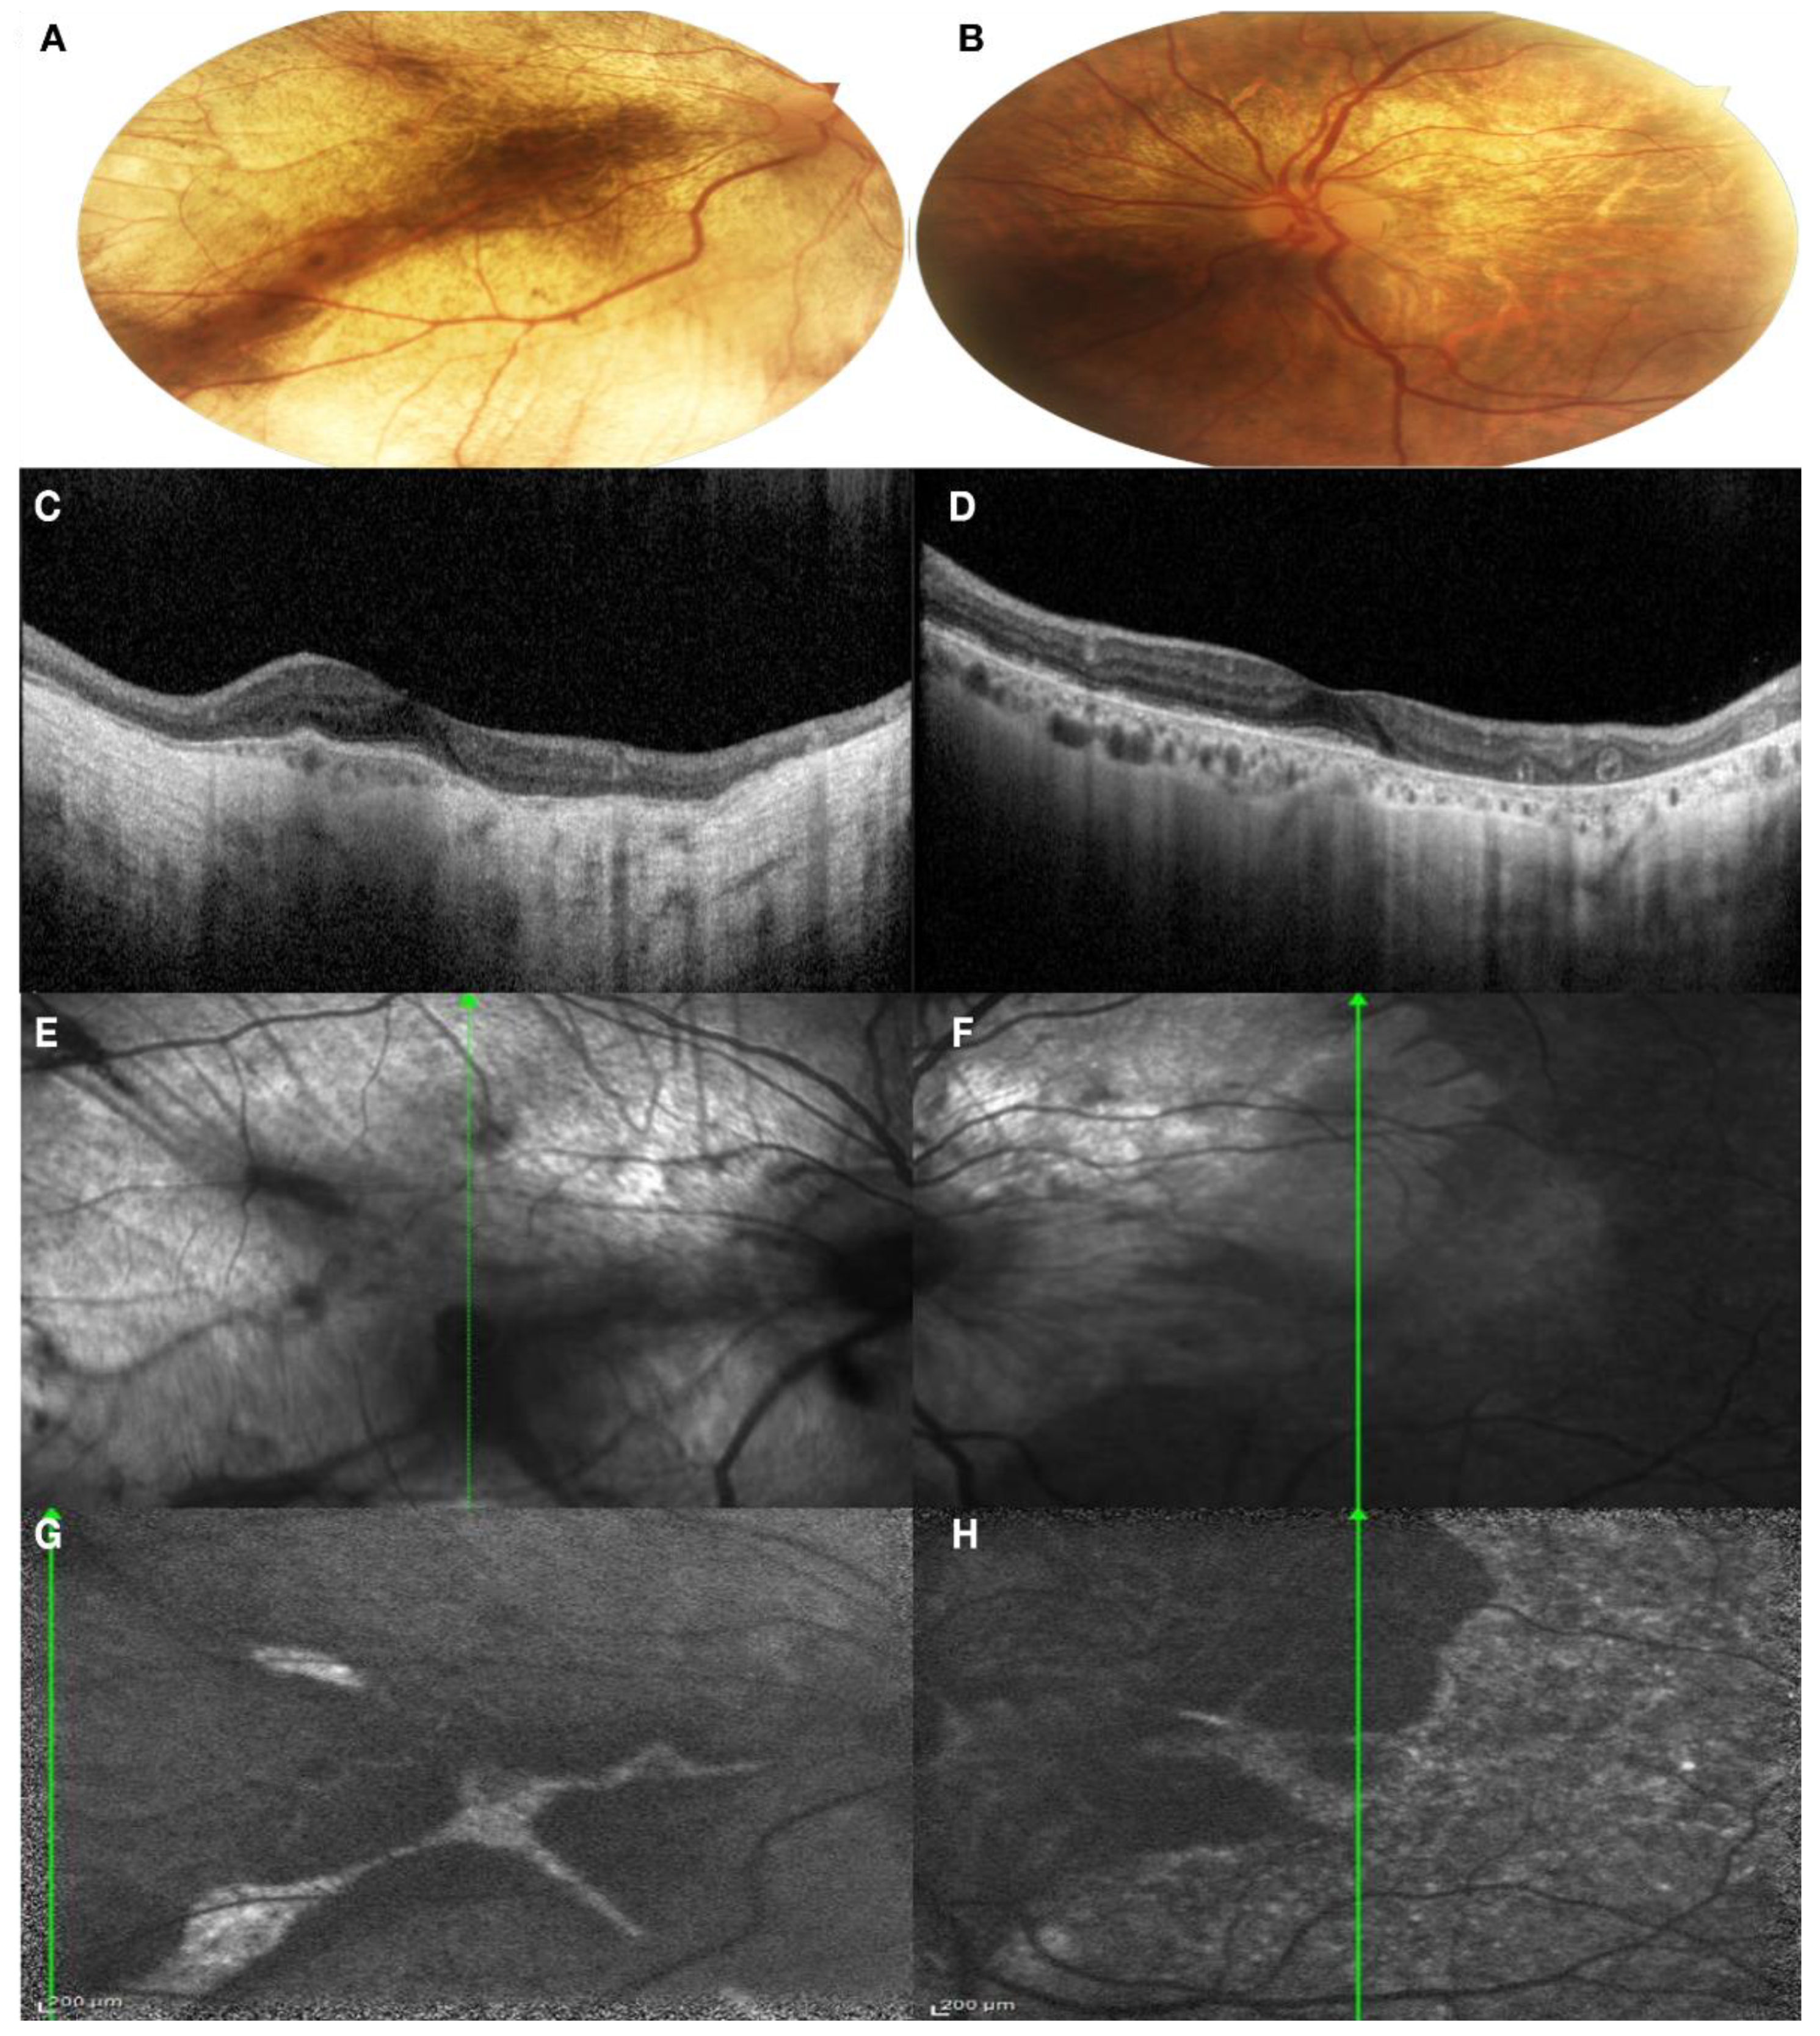

3.1. Clinical Findings